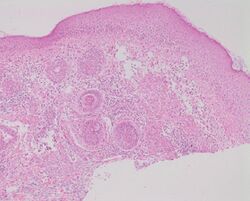

Micrograph showing rosacea as enlarged, dilated capillaries and venules located in the upper dermis, angulated telangiectasias, perivascular and perifollicular lymphocytic infiltration, and superficial dermal edema.[17]